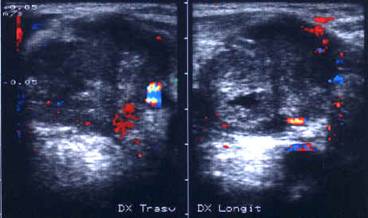

Lobul drept, proiectie trasversala si longitudinala.

Femeie de 29 ani. Nodul de consistenta dura in lobul

drept si istm.

Ecografia: nodul cu margini difuze in lobul drept si istm, care deformeaza

conturul anterior al glandei, structura parenchimatoasa, neoomogena, hipoecogena.

Prezenta de linfonoduli laterocervicali.

Citoaspiratia: carcinom papilar.

Examen histologic: carcinom papilar plurifocale varianta foliculara.